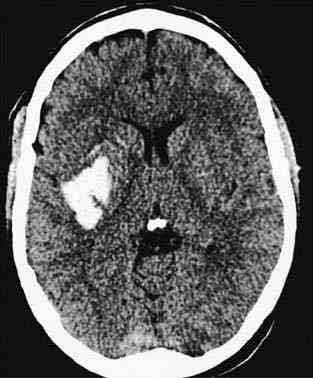

Морфологічно розрізняють гематоми, т . е. порожнини, заповнені рідкою кров'ю і згустками, добре відмежовані від навколишньої тканини, і геморагії з нерівними контурами, чітко не відокремленого — геморрагическое пропотеваніе. Звертає увагу переважна локалізація гематом в області підкіркових вузлів півкуль мозку. Значно рідше гематоми розвиваються в області зубчастих ядер мозочка і ще рідше -у області моста мозку. Формування гематоми відбувається головним чином внаслідок розсовування вилилась кров'ю мозкової речовини і здавлення останнього.

При крововиливі в мозок в 85-90% випадків спостерігається прорив крові в шлуночкову систему або в субарахноїдальний простір. Найбільш типове місце прориву — латерально-базальна частина переднього рогу бічного шлуночка (головка хвостатого ядра). Зустрічаються крововиливи з одномоментним проривом, стінки в різних ділянках шлуночкової системи.

При крововиливах по типу гематоми нерідко виявляють великий набряк мозку, сплощення звивин і розвиток грижових вклиненням мозку. Гематома полушарной локалізації викликає зміщення стовбура мозку з вклиненням його в тенторіальное отвір, наслідком чого є деформація стовбура мозку і розвиток в ньому вторинних дрібних крововиливів.

У клінічній практиці широке поширення набула класифікація крововиливів в залежності від локалізації вогнища крововиливу. Серед паренхіматозних крововиливів розрізняють крововиливи у великі півкулі головного мозку, крововиливу в стовбур мозку і в мозочок. За локалізацією в півкулях крововиливи діляться на латеральні — назовні від внутрішньої капсули, медіальні — досередини від неї і змішані, що займають всю область підкіркових гангліїв.